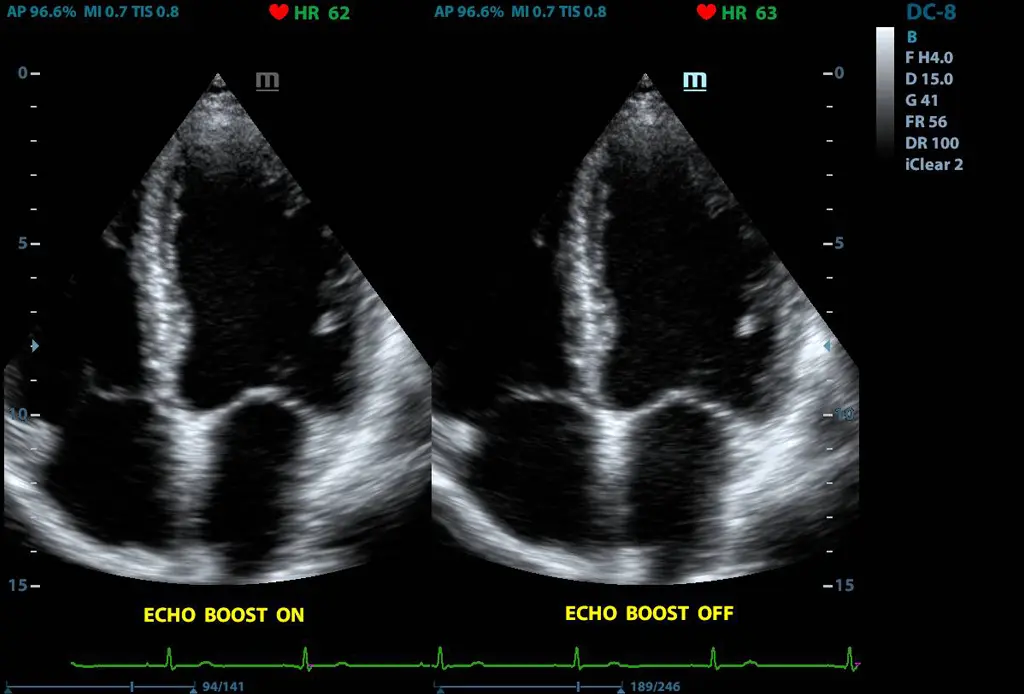

Ehoo Boost

Технология специално създадена за оптимизация на цялостната миокардиална тъкан. Ефективно подобрява контраста на миокарда и разграничването на интимата.

Ehoo Boost

A technique specifically designed to optimize and enhance myocardial tissue, which can effectively improve the contrast between the myocardium and the heart, and improve the display of the intimal boundary.